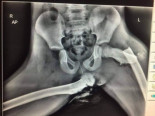

Terrible imagen que muestra por qué nunca debes poner los pies en el salpicadero [ENG]

actualidad

|

etiquetas

:

accidente

,

radiografía

fractura

imprudencia

tráfico